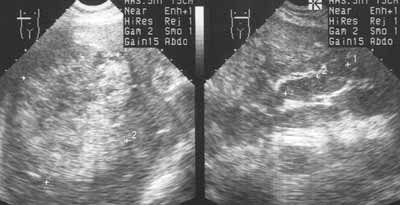

Ультразвуковое исследование в диагностике рака желудка.

Рис. 3. Метастзы рака желудка в печень, опухолевый тромб в воротной вене.

Новости лучевой диагностики 2001 1-2: 37-39